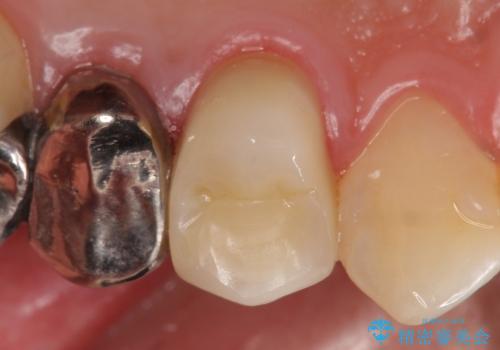

- 歯茎にできものが出来てなかなか治らないので診て欲しいといらっしゃった方の症例です。

診査の結果、左上4番目の歯の神経が死んでおり、根尖に膿が溜まっていることが原因とわかりました。

そのため左上4番目の歯は根管治療を行い、歯茎の膿の出口の消失を確認後、オールセラミッククラウンによる補綴を行いました。